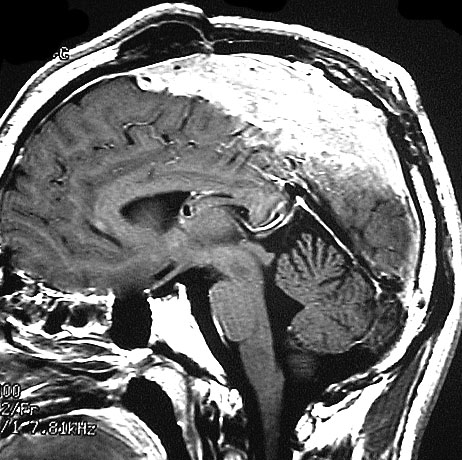

上矢状洞髄膜腫 superior sagittal sinus meningioma

また別な例です。1986年13歳の時に2度の開頭手術を受けましたが,全摘出できずにそのまま経過観察されました。

左の画像は1997年の術前のものです。これを2回に分けて全摘出しました。上矢状洞はやはり冠状縫合のあたりから静脈洞交会まで摘出しました。その下の大脳鎌も全て摘出したので,直静脈洞の上壁を開けることになり,直静脈洞からの激しい出血があり縫合して直静脈洞形成をするのが大変でした。手術後16年が経過しますが再発していませんし,社会人として普通に暮らせています。

この例が教えてくれることは,上矢状静脈洞は全長にわたり切除してしまっても,神経脱落症状を出さないで普通に生きて行かれるということです。